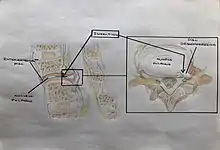

Secondary and tertiary structures

Chymopapain's structure was solved by X-ray diffraction techniques.[3] Analysis of this structure showed chymopapain to have 7 alpha helix regions, 10 beta sheet regions and 2 loop turns.[3] These 2 turns are the main difference between chymopapain's structure and other papaya proteinase proteins such as papain or caricain, which have similar conformations.[11][12]

Besides, chymopapain presents 3 disulfide bonds as post-traducional modifications stablished between residues 156–197, 190–229 and 287–338.[3]

Quaternary structure

Chymopapain presents a quaternary structure characterized by the formation of homo dimers, which means that two chymopapain chains join each other through weak interactions to conform one unique biological structure.[10]